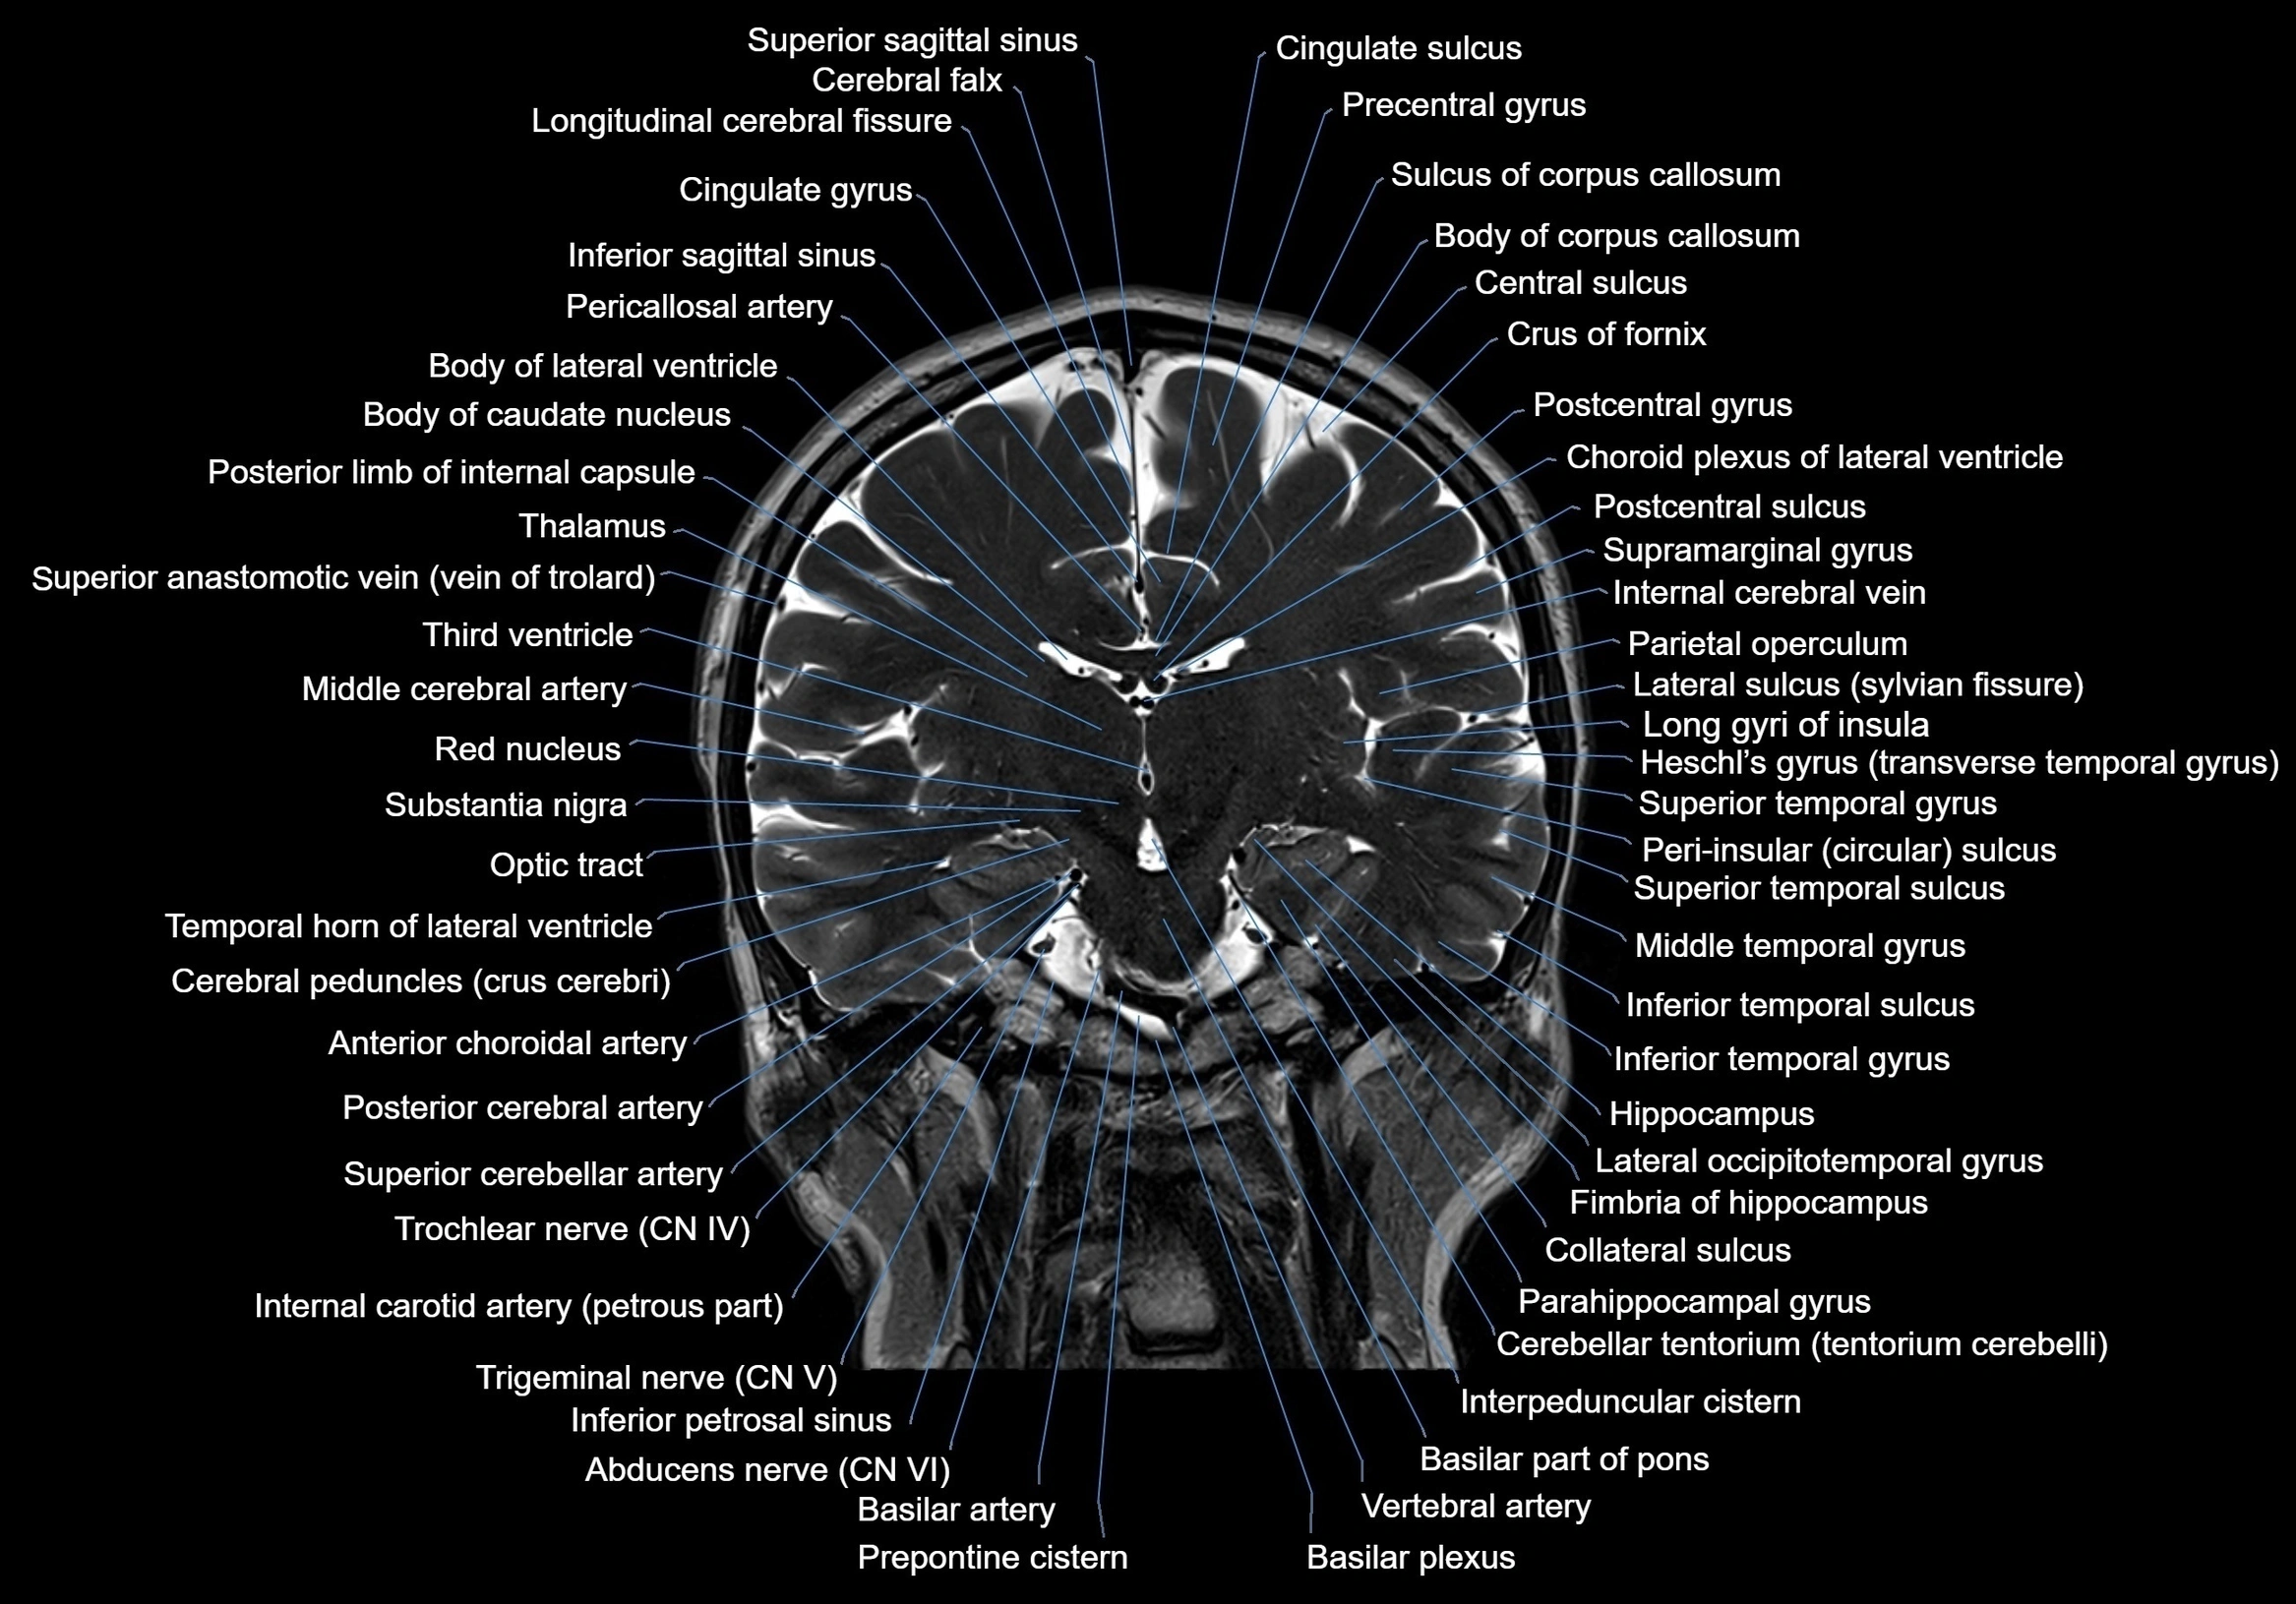

MRI images